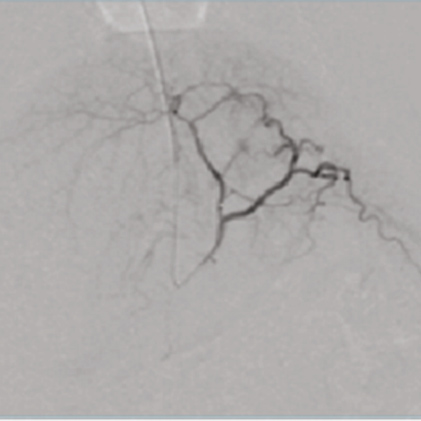

DSA(Digital Subtraction Angiography) helps various clinical diagnosis and procedures through the vessel image information after injecting contrast medium.